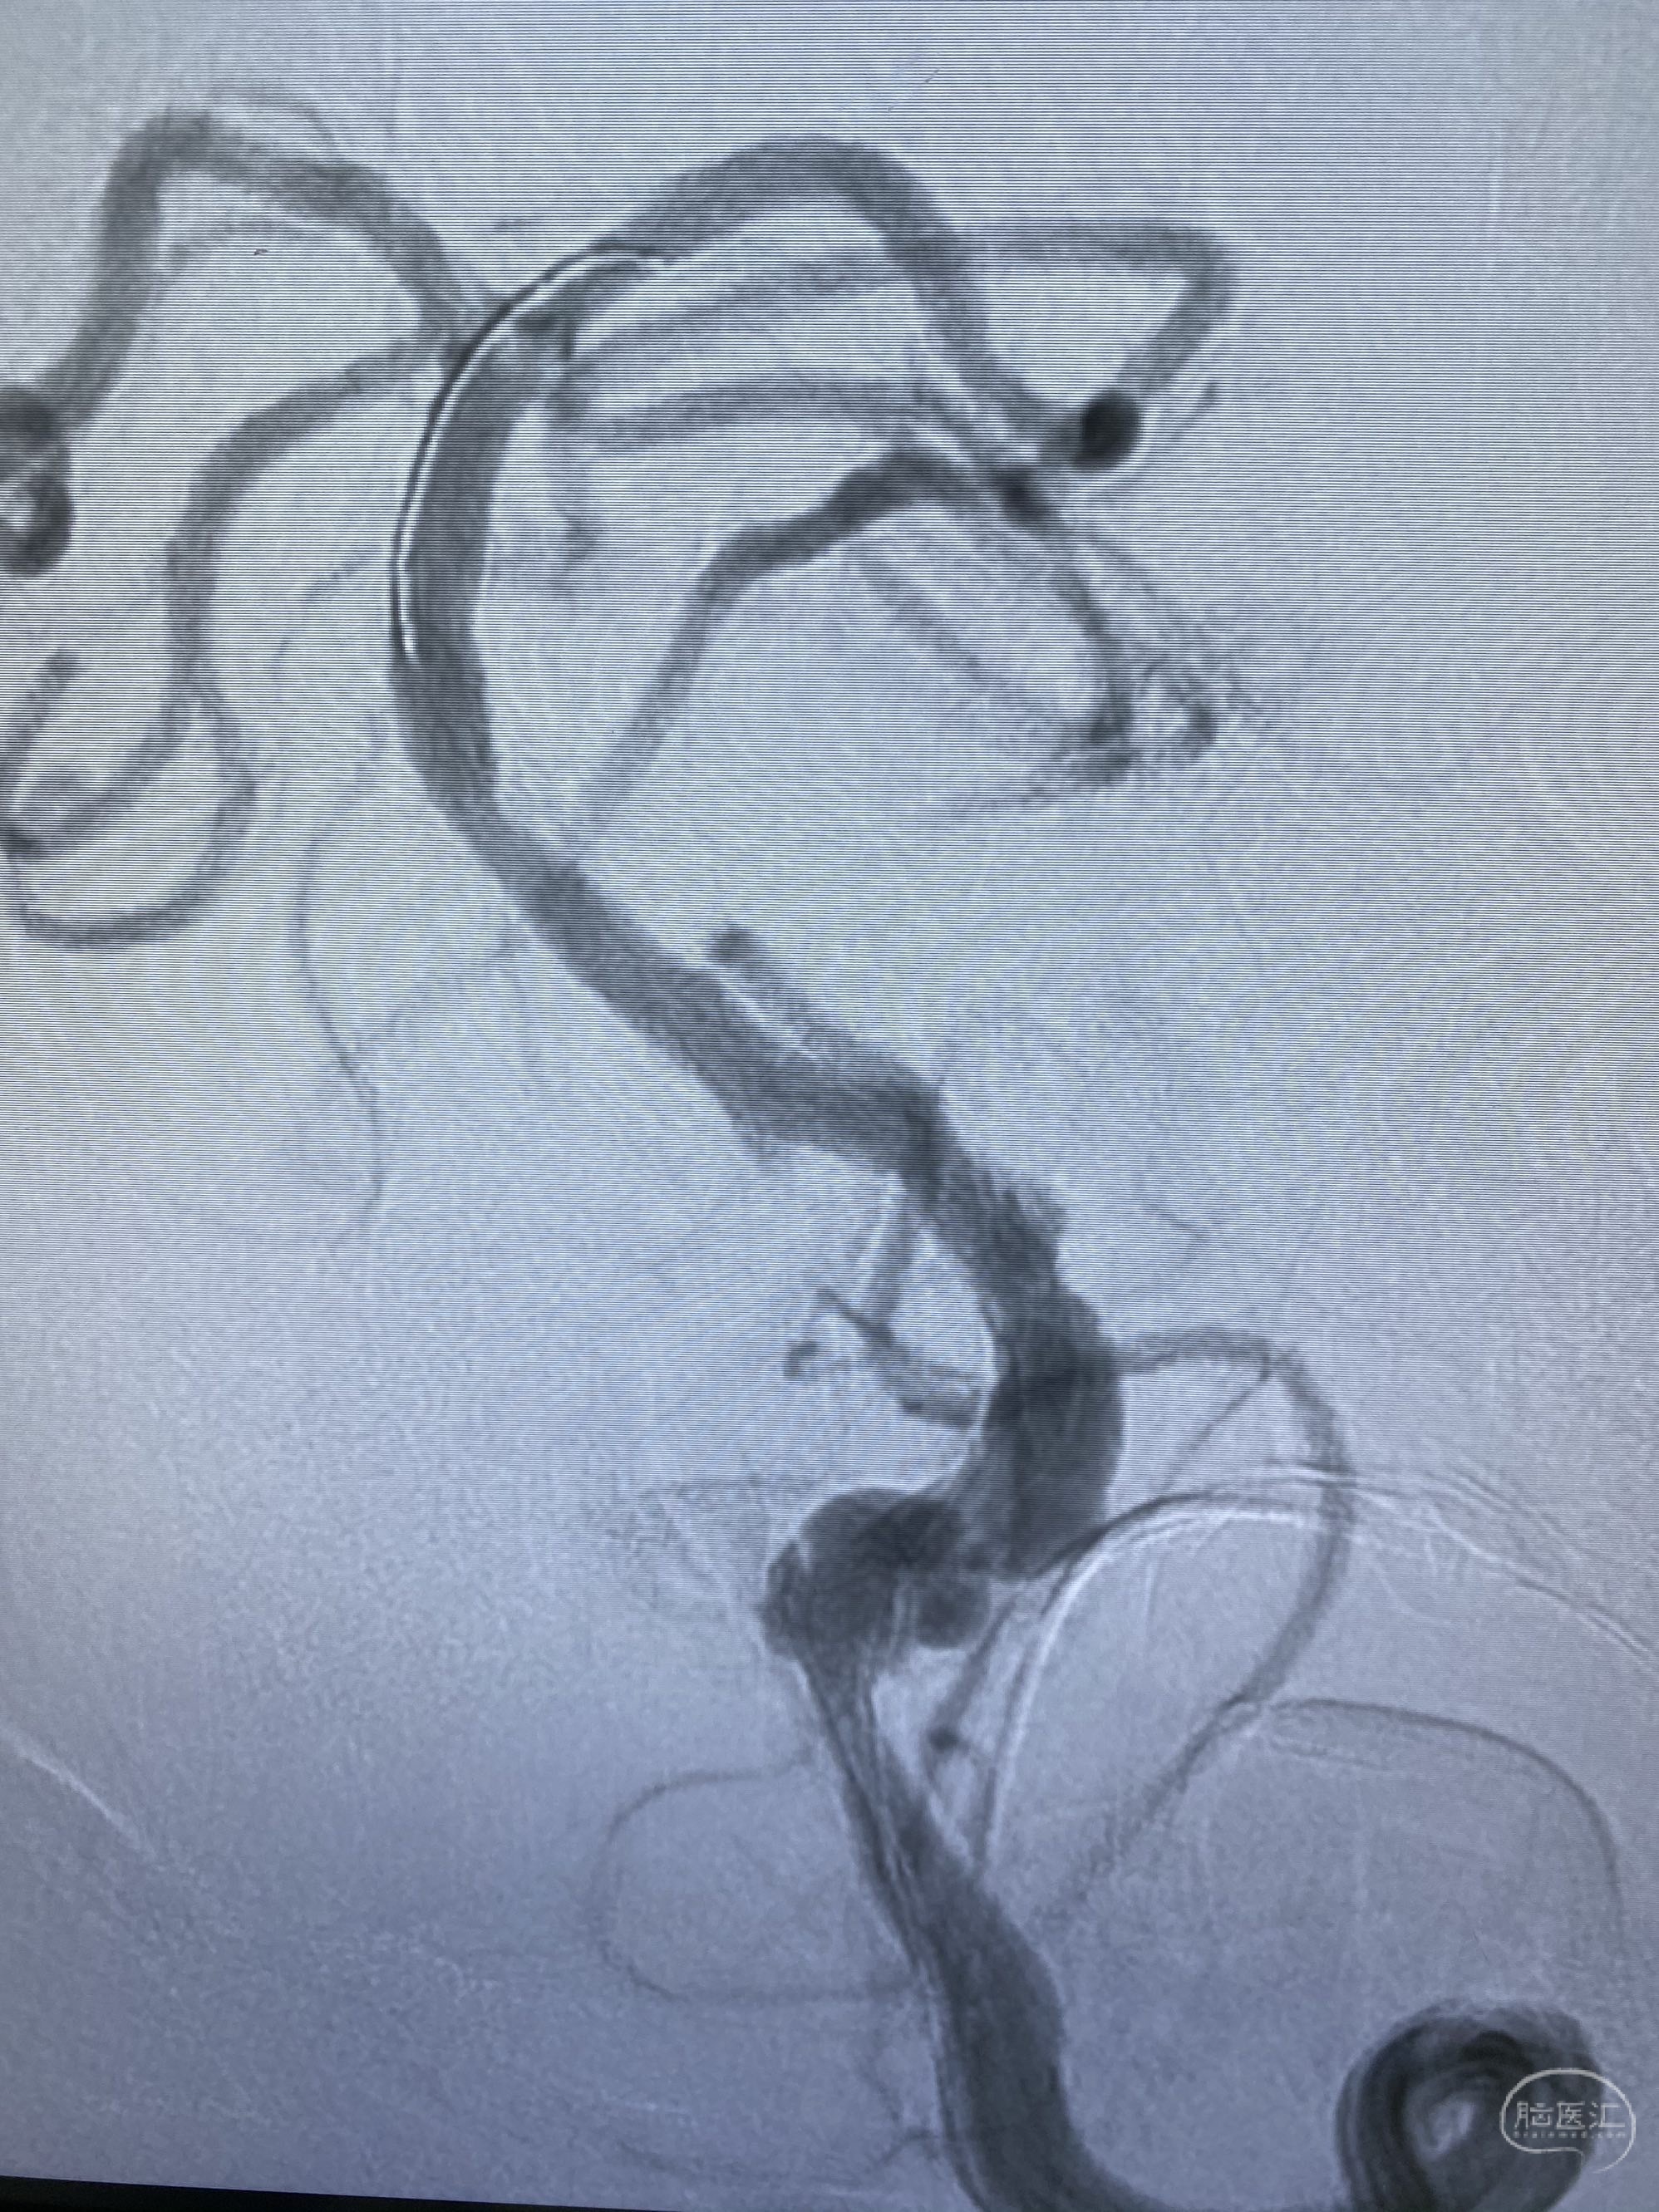

今日手术,TJG,M62Y,一期左侧颈动脉狭窄支架植入,二期椎动脉V4段多发夹层动脉瘤伴狭窄,常规支架辅助栓塞方法复杂又危险,血流导向装置植入快捷又安全。南阳市中心医院神经内科脑血管病介入团队pipeline flexFD植入两人导师资格。

椎动脉颅内段多发夹层动脉瘤伴载瘤动脉狭窄pipeline flex植入

今日手术,TJG,M62Y,一期左侧颈动脉狭窄支架植入,二期椎动脉V4段多发夹层动脉瘤伴狭窄,常规支架辅助栓塞方法复杂又危险,血流导向装置植入快捷又安全。南阳市中心医院神经内科脑血管病介入团队pipeline flexFD植入两人导师资格。